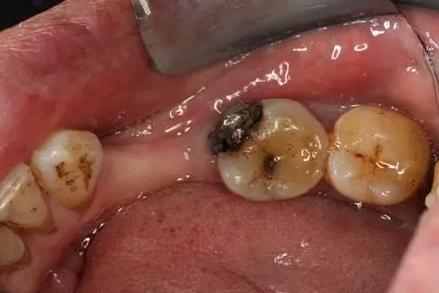

顾名思义,“根面龋”指的是发生在牙根的龋齿。一般情况下,牙根是被牙龈包住形成一种保护的。但人们随着年龄的增大,会出现生理性的牙龈退缩,牙根部位开始暴露。而相对于牙冠来说,牙根部位缺少了牙釉质的保护,所以硬度会相对较低,且容易附着牙菌斑,不容易清洁,更加容易发生龋坏。

而根面龋的位置比较隐蔽,在浅龋或中龋的阶段并不会有什么不适、也不容易被发现所以常常被忽视。据相关数据显示,在中老年人群中,35~44岁年龄阶段的人当中有10.9%存在根面龋;而65~74岁的老年人近40%存在根面龋的情况!但根面龋得到治疗的比例不足3%。

很多人发现根面龋是因为日常吃东西时感到经常塞牙或者“刮舌头”,去看牙医通过检查口内、拍牙片才得知,这时候一般根面龋已经形成了一个大龋洞了。若不及时治疗,将会形成牙髓炎,严重者牙根会折断。